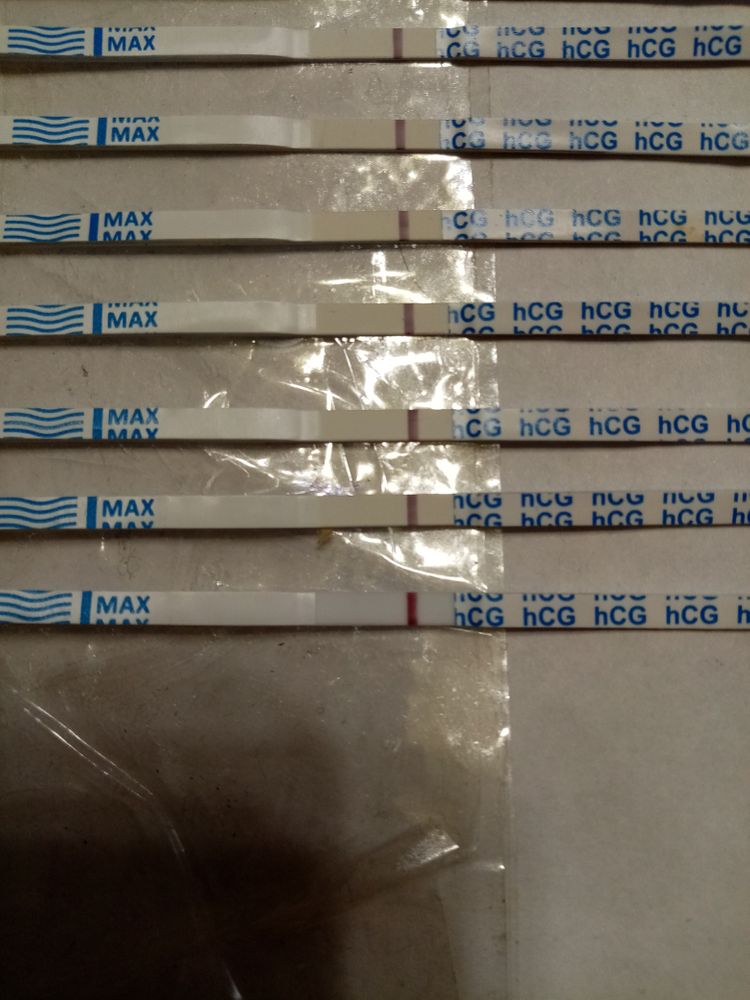

Укол хгч, сведёт с ума эти тесты.

Был укол хгч 25000 МЕ, позовчера сдавала кровь, результат 5,7, ну понятно что хвост. Вчера тесты уже были пустые, да и сегодня утром и днём. Да, у меня 12 д.у и 9-10д.п.о.Сейчас сделала и опять призрок, это все от укола что-ли?

Тесты кстати хорошие,хоть все и говорят что реагенты выдают,но вот наглядный пример того что они могут быть пустыми .

Анютка Никулча, обязательно дождётесь,вот у меня на 3 дз.Сейчас 5 и он слабый только что сделала.Этот же тест